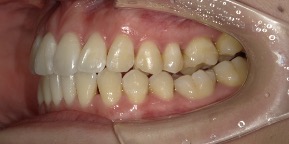

33歳女性のビフォーアフター

| 診断 | 空隙 |

| 治療方針 | 治療方針:前歯の咬合関係改善と空隙閉鎖を主な目的にて主にIPR(歯と歯の間をわずかに削合してスペースを獲得する方法)を組み込んだ動的矯正治療を行い、空隙、前歯咬合を改善後、保定を行う。臼歯部の咬合関係はプランの都合上維持することとした。 |

| 治療費 ※ | 67万8千円(診断、型取り、矯正中のメンテナンス、保定装置を含む料金) |

| 治療期間 | 6か月 |

| リスク | 1日20時間以上マウスピースを使用できない場合、歯が動かなかったり、想定しない誤差により不完全に終わる可能性がある。装着時や食事時に痛みを伴う。歯肉退縮や虫歯になるおそれがある。また、指導通りに装着できていない場合や適切なブラッシングが出来ていないとそのリスクが高くなる。歯根が短くなることがある。ごくまれに歯の神経が損傷してしまうことがある。過去にぶつけたり深い虫歯治療をしたことがあるとそのリスクはやや高くなる。矯正後には保定装置が必要。適切な使用ができない場合、後戻りの原因となる。将来的に歯並びが動いて再矯正が必要な場合がある。親知らずが正常に生えていない場合、その可能性がやや高くなる。 |